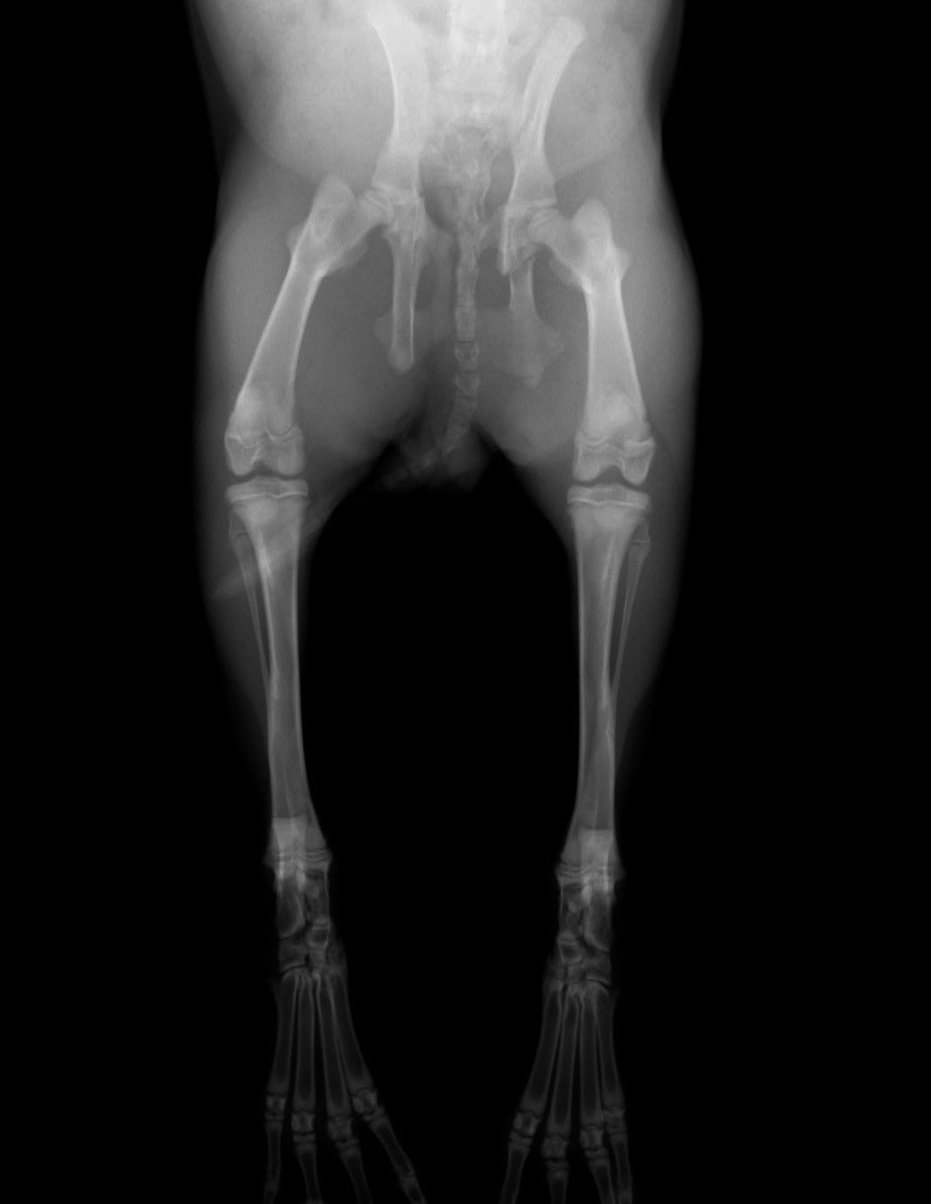

1ヶ月後のレントゲン写真

骨盤の亀裂がふさがって肥厚して、内側に入り込んでいるのがわかります。

ウサギの糞は比較的小さいのでこれぐらいの狭窄であれば問題ないでしょう。出産困難になる場合がありますので妊娠は避けた方がよいです。歩行も問題ないと思われます。